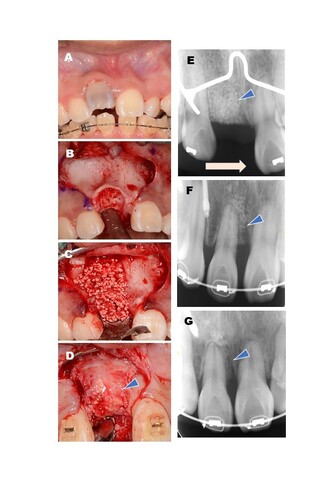

幼少期の外傷により、歯の根と骨が癒着してしまった患者さんのケースでは、問題となる歯を抜歯し、欠損部にサイトランスを用いて矯正治療のための骨の土台を再建。その後、矯正の力をかけることで隣の歯を予定した位置まで移動させることに成功しています。審美的な観点からも注目されていて、今後は矯正治療への応用も広がると期待されています。

矯正治療への対応例。